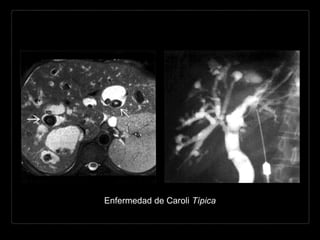

Hallazgos por RM

• T1: dilataciones

saculares hipointensas,

múltiples y pequeñas

• T2: hiperintensas

• T1 + C: reforzamiento

de los radículos entre la

VBIH dilatada

• CPRM: múltiples

estructuras ovaladas

hiperintensas

• continuidad con la vía

biliar

• contenido

hiperintenso de los

conductos biliares en

contraste con la vena

porta, que aparece

como ausencia de la

señal.

Enfermedad de Caroli Típica